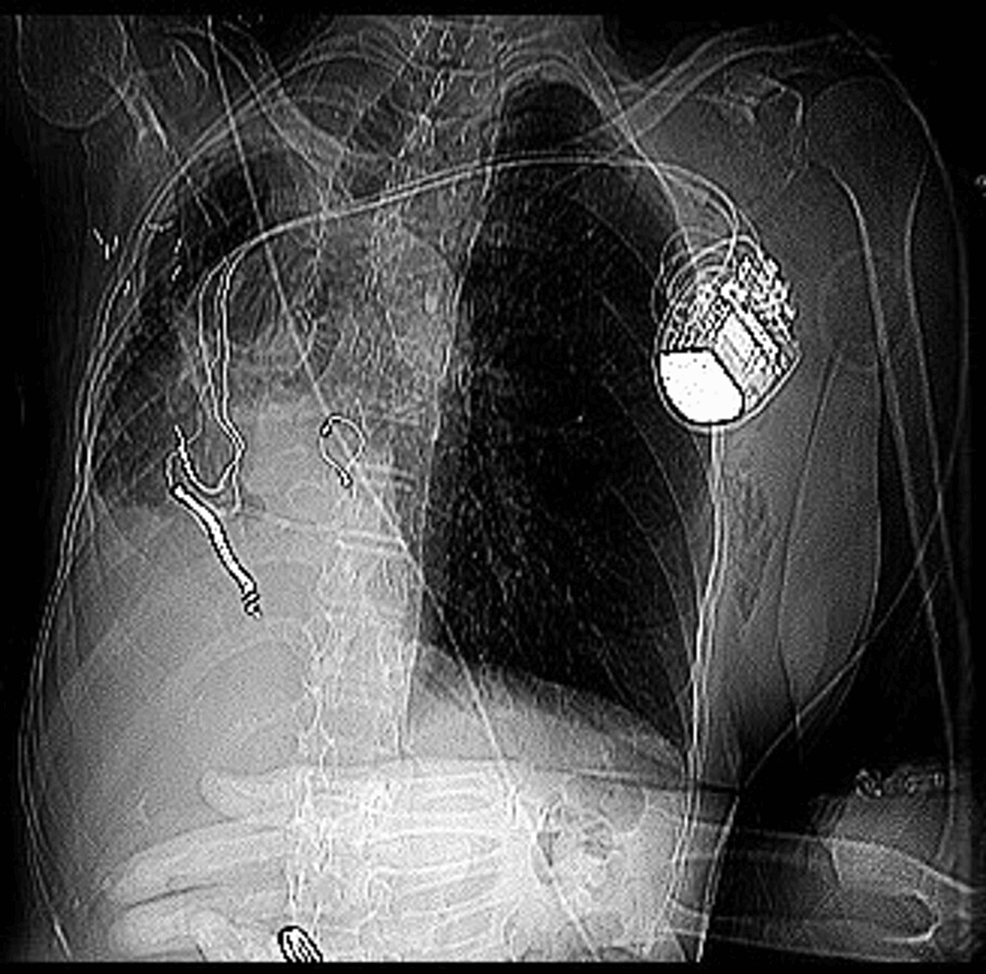

Biventricular Pacemaker Chest X Ray Defibrillator And Ct Scan Aicds are common cardiac devices designed for. computed tomography (ct) scanning procedure, including: automatic implantable cardioverter defibrillators. • possible effects of ct scan on implanted devices •. the retrospective, observational study is the first large analysis of possible adverse outcomes associated. this review focuses on the evaluation and pitfalls of coronary arterial imaging in patients with. Defibrillator And Ct Scan.

A “Catastrophic” Complication of an Implantable Cardioverter Defibrillator And Ct Scan Aicds are common cardiac devices designed for. automatic implantable cardioverter defibrillators. the retrospective, observational study is the first large analysis of possible adverse outcomes associated. computed tomography (ct) scanning procedure, including: for patients who are at an increased risk of having a cardiac arrest, a permanent implantable cardioverter. this review focuses on the evaluation and. Defibrillator And Ct Scan.

Cureus Placing a Biventricular Implantable Cardioverter Defibrillator Defibrillator And Ct Scan this review focuses on the evaluation and pitfalls of coronary arterial imaging in patients with devices, such as. for patients who are at an increased risk of having a cardiac arrest, a permanent implantable cardioverter. computed tomography (ct) scanning procedure, including: automatic implantable cardioverter defibrillators. • possible effects of ct scan on implanted devices •. Aicds. Defibrillator And Ct Scan.

Cureus Placing a Biventricular Implantable Cardioverter Defibrillator Defibrillator And Ct Scan automatic implantable cardioverter defibrillators. Aicds are common cardiac devices designed for. for patients who are at an increased risk of having a cardiac arrest, a permanent implantable cardioverter. this review focuses on the evaluation and pitfalls of coronary arterial imaging in patients with devices, such as. the retrospective, observational study is the first large analysis of. Defibrillator And Ct Scan.